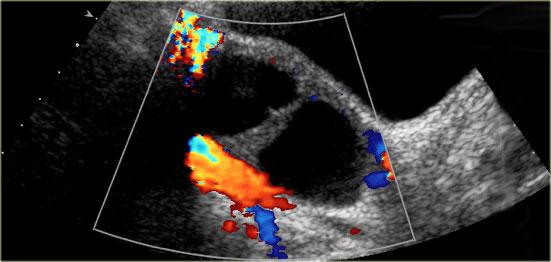

Ngoài ra, khả năng tổn thương tân sinh là ác tính cũng tăng theo kích thước tổn thương. - Vách ngăn có mạch máu

Sự hiện diện của vách ngăn gợi ý khả năng tân sinh. Khi vách ngăn có độ dày hơn 3mm và có mạch máu rõ – mặc dù không đặc hiệu – cả hai đặc điểm này đều làm tăng khả năng tổn thương tân sinh là ác tính. - Thành phần đặc có mạch máu